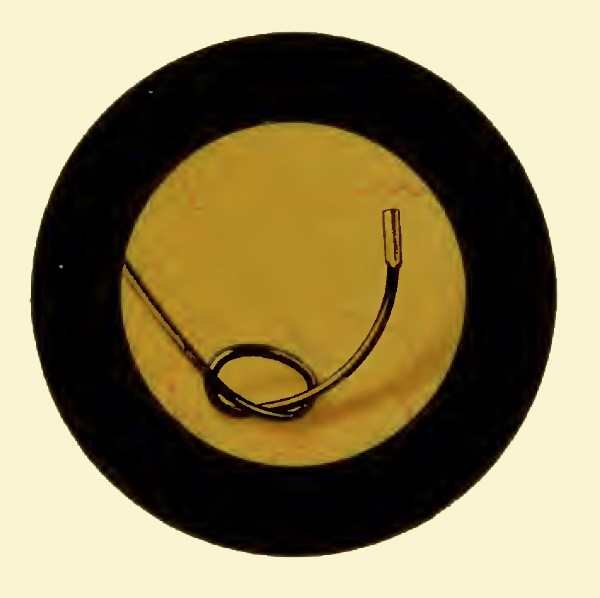

Pictured below is a hook specifically designed by Gentile of Paris for removing hairpins from the female bladder (1905 Catalogue).